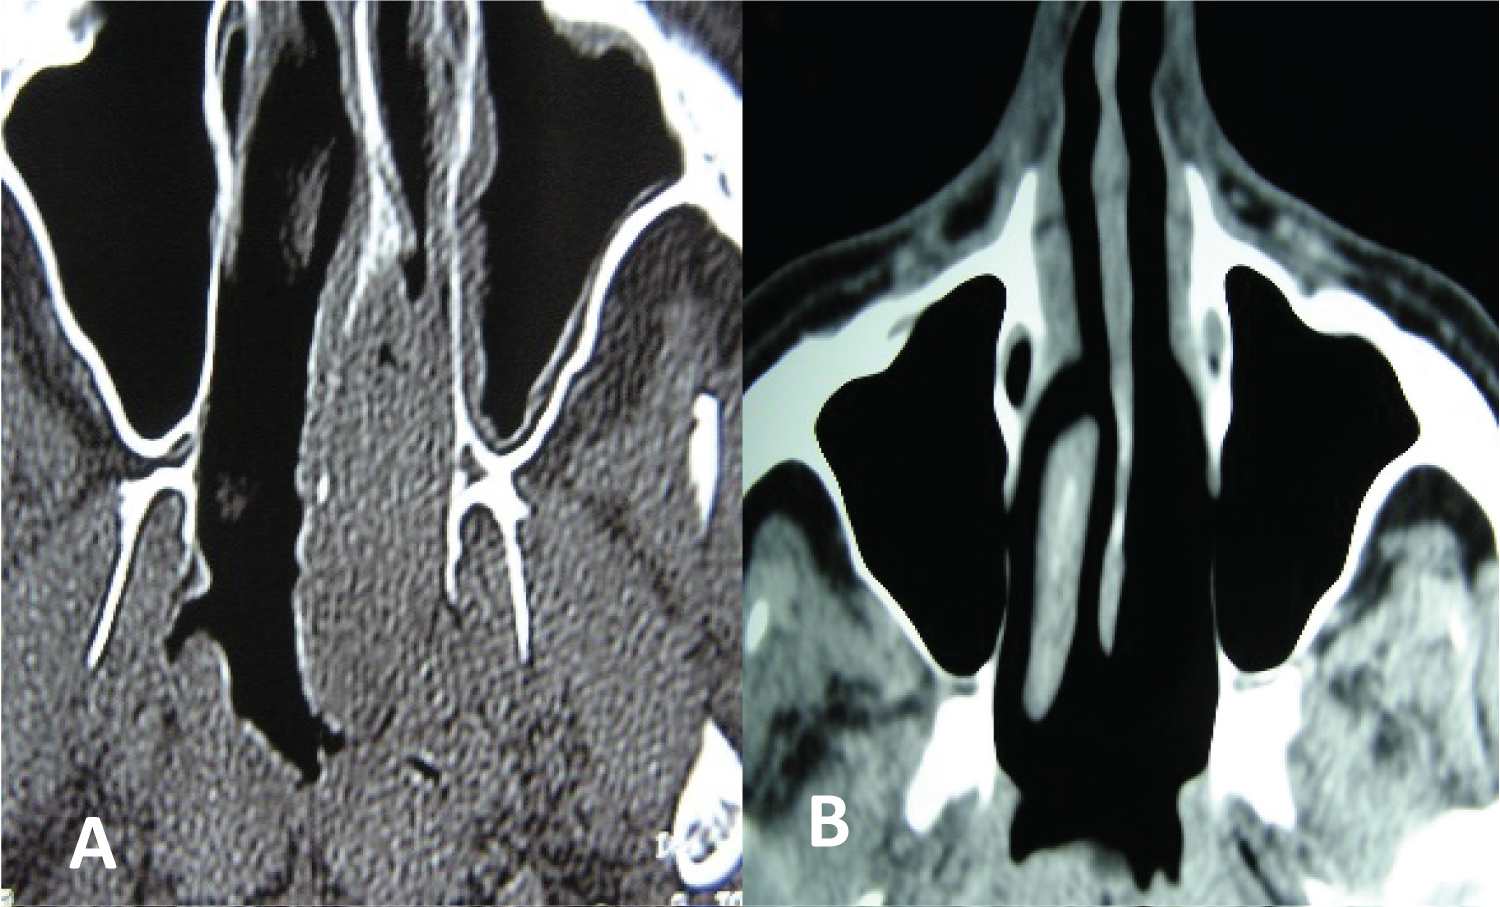

It was confirmed that the resection was complete by the intraoperative histological study of the surgical margins (Figure 1 and Figure 2).

Figure 1: Metastasis of clear cell renal adenocarcinoma in the posterior third of the nasal septum. Endonasal resection with endoscopes (A) Pre and (B) Postoperative. View Figure 1

Figure 2: Clear cell renal adenocarcinoma metastasis in the inferior turbinate. Endonasal resection with endoscopes: (A) Tomography and; (B) Surgical specimen. View Figure 2